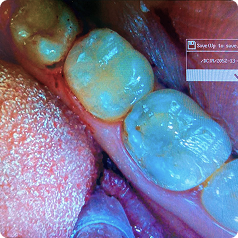

Лечение кариеса

Рыбин В. А.